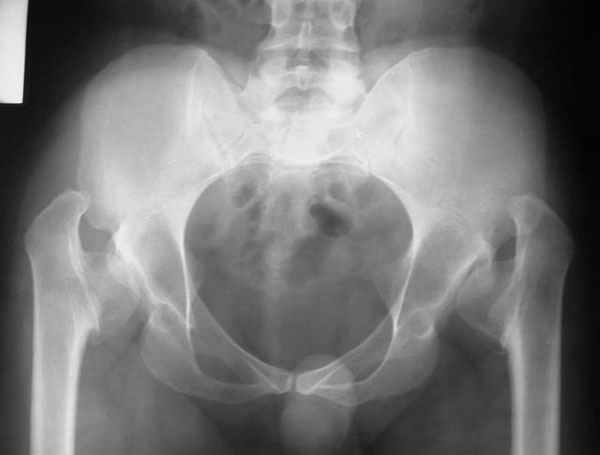

It appears that this patient has bilateral congenital hip displasia, as presented on the radiographs. As shown, the problem involves both sides of the hip joint: the acetabulum and proximal femur.

This patient is noted to have a very vertical joint surface orientation, as well, with retroversion of the acetabulum.

In a hip with normal version, (on discussion list) Hip Pain (Dr.Kullerkann) the lines connecting the anterior and posterior acetabular wall as seen on an AP radiograph usually intersect at one point near the superior and lateral portion of the acetabulum. As an example of an abnormal hip, a patient with a retroverted acetabulum will show the figure 8 pattern, with the two shadows crossing over the femoral head. In this particular patient, again it appears that there is a significant amount of retroversion of the acetabular wall, as the anterior wall appears to be more anteriorly displaced than in a normal hip.

Typically, patients begin to have hip pain after adolescense depending upon the level of activity and weight of the patient. If untreated, this problem ultimately results in the need for total hip arthroplasty, which can often be difficult in a dysplastic hip. Reconstructive surgery, if performed early, can lead to many years of functional improvement and, potentially, a delay in the need for arthroplasty.

In this patient, it appears that addressing either the femur or the acetabulum will be insufficient to help correct this patient’s problem. It would be necessary to approach both sides of the hip joint to correct the hip dysplasia.

Depending upon surgeon preference, as well as availability of adequate operating room equipment and staff, this reconstruction can be done in two stages: periacetabular osteotomy with correction of acetabular retroversion would be the first stage. The second stage would involve a proximal femoral valgus osteotomy with neck lengthening.

In this second stage, a 120 degree blade plate can be used for correction proximal femur varus deformity. These procedures are both technically difficult, and require a great amount of pre-operative planning, both by the surgeons involved as well as the operating room staff.

The pre-operative planning would need to be done with the use of more radiographs for assessment of the hip dysplasia. These x-rays include a repeat AP pelvis, separate AP and lateral of the hips, long-standing femoral axis views of both legs, false profile view, as well as abduction and adduction films.